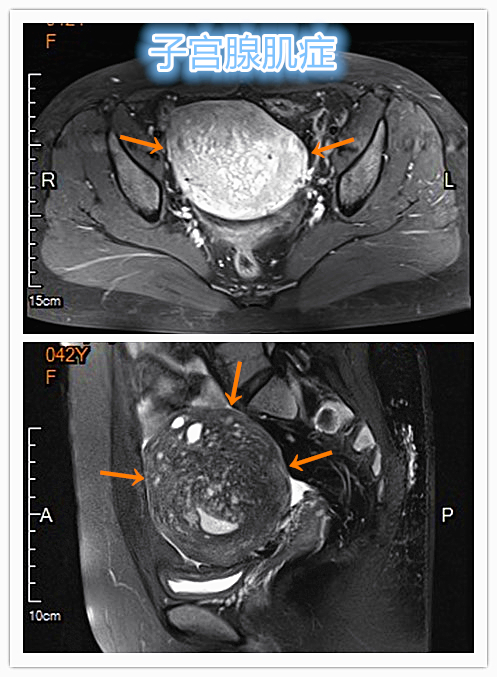

青年女性患者,反复痛经、经期延长5年余。确诊为子宫腺肌症,经妇科保守治疗症状无改善,病情进行性加重。经介入微创治疗后症状得到逐步缓解。

MRI显示子宫明显增大